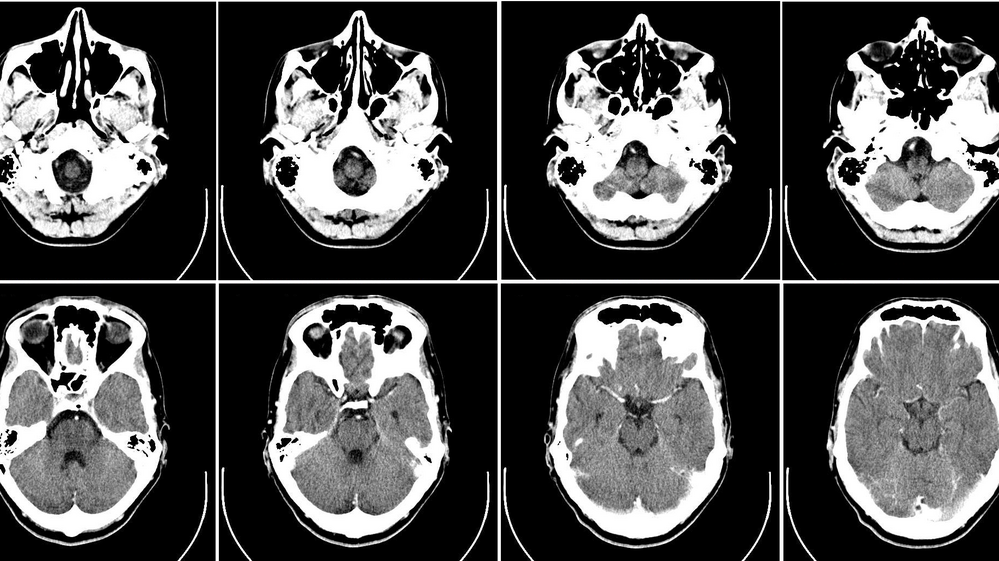

Radiologist and hospitalists collaborated on an experiment to see if disclosing the cost of some of the most frequently ordered imaging tests, including standard chest X-rays and CT scans of the head, would reduce their use in the hospital.

Telling doctors that a head CT would cost $229.95, for instance, didn't do much to affect the number of scans done during a six-month period when its price was revealed compared with a similar period when the price wasn't displayed on computerized ordering screens.